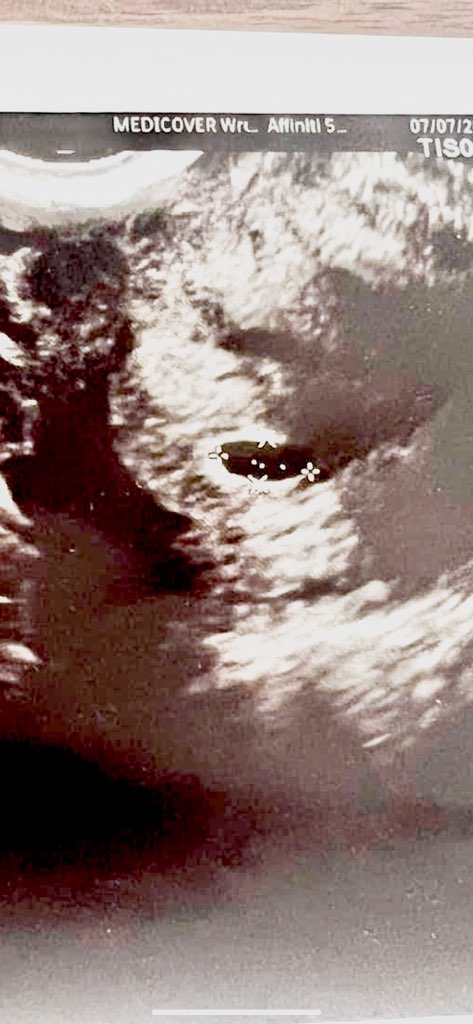

Screenshot_20230708_092743_Gallery.jpg

Cześć dziewczyny! Przyłączam się do Was! 🥰 To jest moja 4 ciąża, ale mam tylko 1,5 rocznego synka na pokładzie. Jestem mega szczęśliwa, bo kompletnie się do tego nie przykładaliśmy, była zasada ze jak będzie to będzie, a jak nie to też fajnie ;) Pozdrawiam i zadaje standardowe pytanie... Jak się czujecie? 😂 Zobacz załącznik 1544709

to z OM bedziesz miala 5+2, czasem moze jeszcze byc tylko sam pecherzyk 🙂